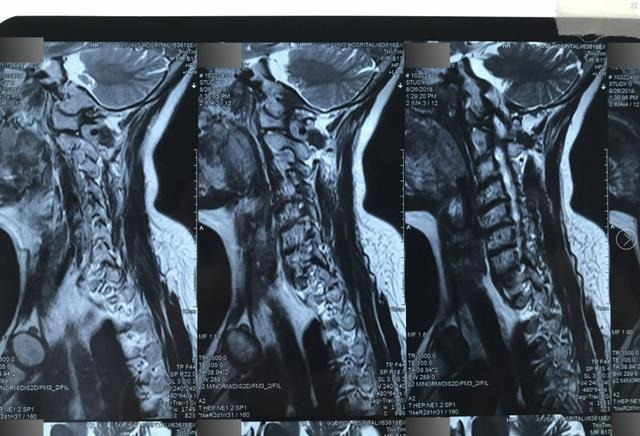

10。因此,有必要将磁共振膜放入部分扩大的区域,并尽可能清楚地了解膜上的细节。如图21所示,分隔了磁共振膜。

(图21)

11。以序列进行分配的磁共振图像以获得以下相对有价值的清晰图片(图21-1,图21-2,图21-3,图21-4,图21-5,图21-5,图21-6,图21-7,图21-8)